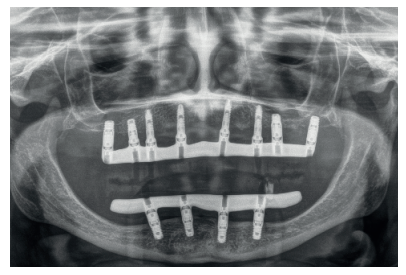

Presentamos el caso de una mujer de 67 años que acude a la consulta para solicitar un tratamiento que mejore la estética y la funcionalidad de las prótesis removibles que porta. En la radiografía panorámica inicial se observan dos implantes en la región anterior mandibular que actualmente no están formando parte de la rehabilitación, que en algún momento sostuvieron una barra para una sobredentadura (Figura 2). En la imagen de sonrisa e intraoral podemos ver la prótesis removible superior e inferior deteriorada y con zonas fracturadas (incisivo central superior derecho) (Figura 3). Al retirar las prótesis podemos observar los implantes con dos tornillos fracturados en su interior (Figura 4).

Se realiza un CBCT dental para la planificación del caso y poder rehabilitar el maxilar superior e inferior. En la mandíbula se planifica retirar los dos implantes de forma atraumática (mediante el kit de extracción a contra-torque) y la inserción de cuatro implantes para la confección de una nueva prótesis implanto-soportada. Los cortes de planificación muestran la necesidad de que los implantes insertados sean cortos y algunos de ellos, como el caso del implante en posición 44, por lingual del nervio dentario. (Figuras 5-7).